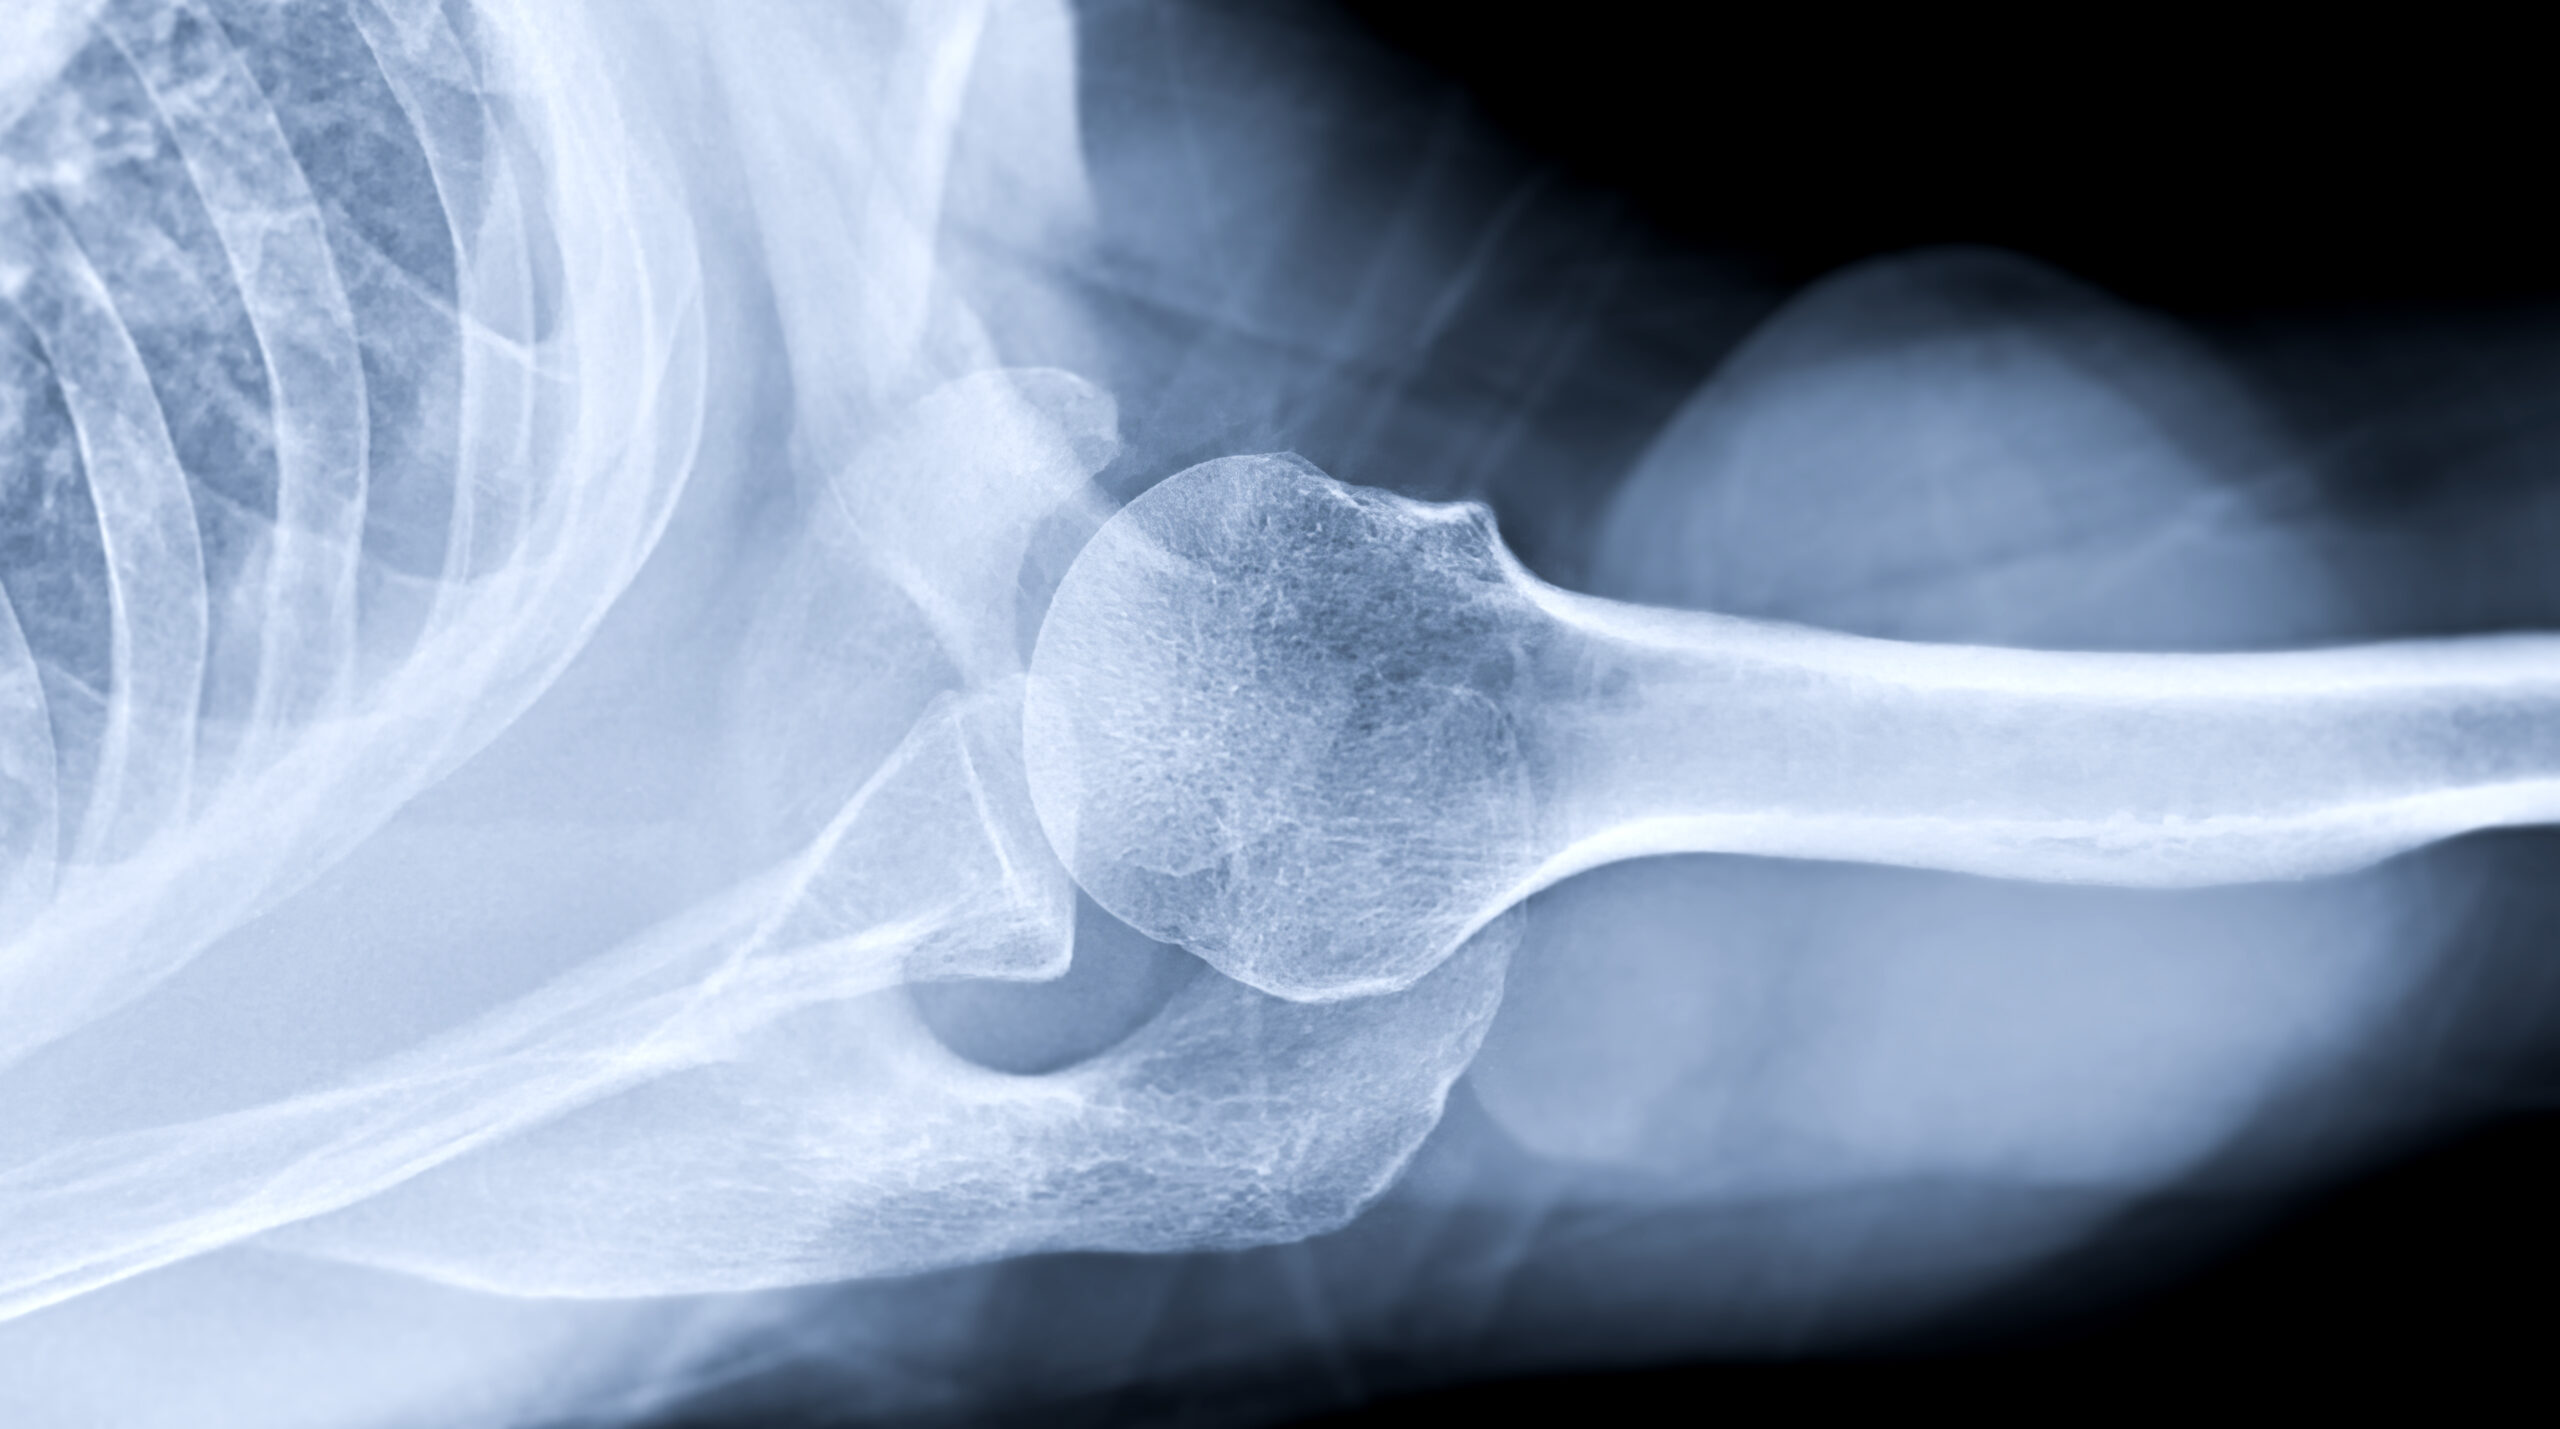

3.検査・診断

患者様の症状に対するお悩みや身体の状態を正確に把握するため、問診や触診、レントゲン撮影等で精密検査を行います。より精密な検査が必要と判断した場合は、連携医療機関へ紹介させていただくことがあります。